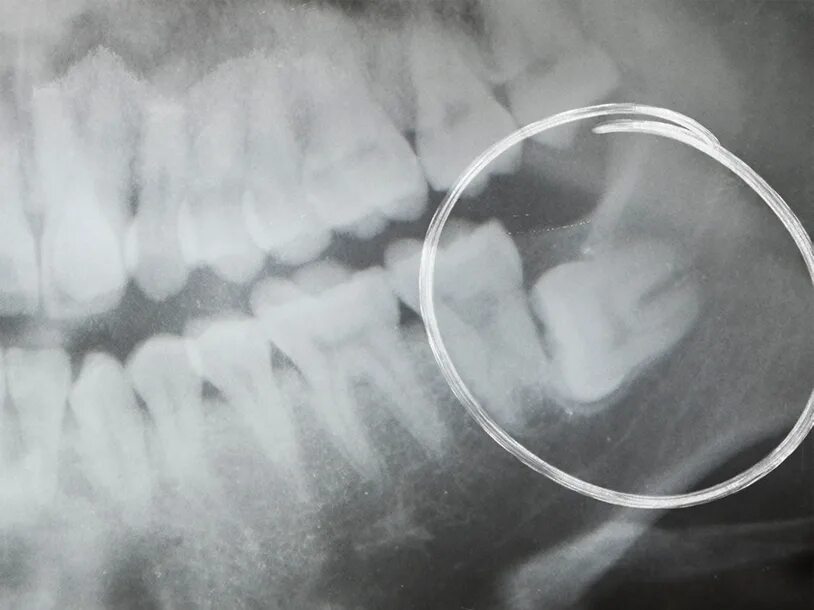

Могут ли быть 9 зубы